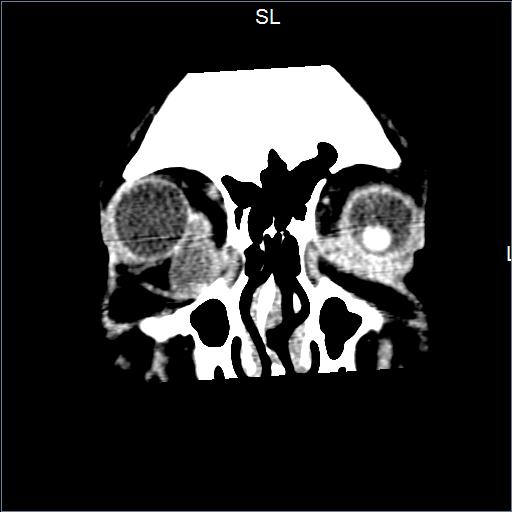

Padecimiento actual de 2 años de evolución caracterizado por sensación de cuerpo extraño, epífora y proptosis en ojo derecho.

A la exploración física con limitación a levoducción e infraducción en ojo derecho

Se realizaron estudios de imagen que detectaron tumor en órbita.